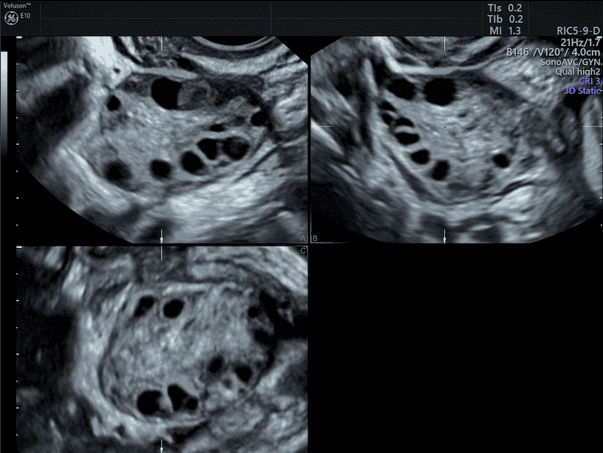

รังไข่มีถุงไข่ขนาดเล็กหลายๆใบจากอัลตราซาวด์

5️⃣ อัลตราซาวด์พบถุงไข่หลายใบ

รังไข่จะมีลักษณะถุงไข่เล็ก ๆ หลายใบเรียงรอบขอบรังไข่

การตรวจประเมินจะรวมถึงการซักประวัติ ตรวจเลือดฮอร์โมน และอัลตราซาวด์รังไข่